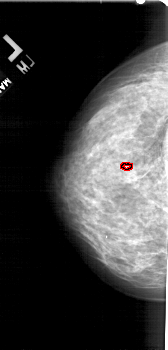

FILE: A_1755_1.LEFT_MLO.OVERLAY

TOTAL_ABNORMALITIES 1

ABNORMALITY 1

LESION_TYPE CALCIFICATION TYPE PLEOMORPHIC DISTRIBUTION CLUSTERED

ASSESSMENT 4

SUBTLETY 1

PATHOLOGY BENIGN

TOTAL_OUTLINES 1

BOUNDARY